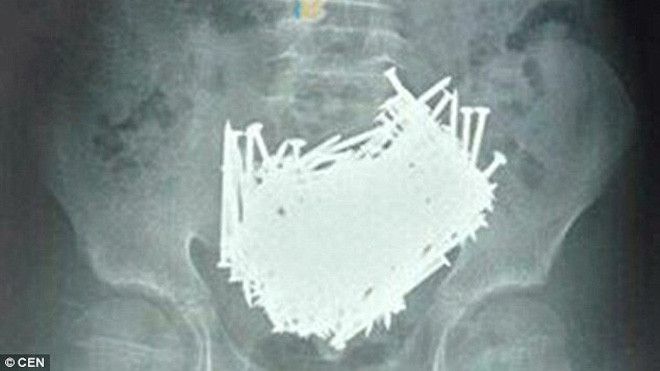

Hình chụp CT cho thấy 200 chiếc đinh nằm trong bụng cậu bé 15 tuổi

TPO - Cầm kết quả chụp CT trên tay, các bác sỹ ở Trung Quốc hoảng hốt khi thấy có tới 200 cái đinh nằm trong bụng cậu bé mới 15 tuổi.

Sau khi chụp CT, các bác sỹ thấy rất nhiều dị vật trong bụng bé. Các bác sỹ ngay lập tức đưa em tới phòng phẫu thuật, lấy ra hơn 200 chiếc đinh, tăm xỉa răng, đá và tiền xu trong bụng em.

200 chiếc đinh được lấy ra khỏi bụng cậu bé